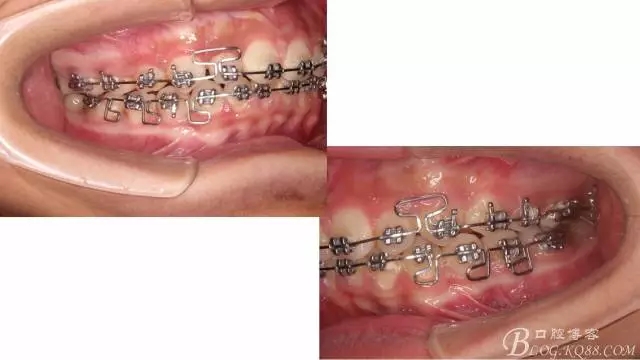

佩戴三個月的FR2, 效果奇佳!前牙基本達到淺覆蓋,淺覆合!接下來進入二期直絲弓固定正畸,排齊階段!

接下來盡管配合些雙側(cè)后牙對角牽引,咬合關系依,不盡人意。

下頜配合多曲方絲,三角牽引,調(diào)整咬合。